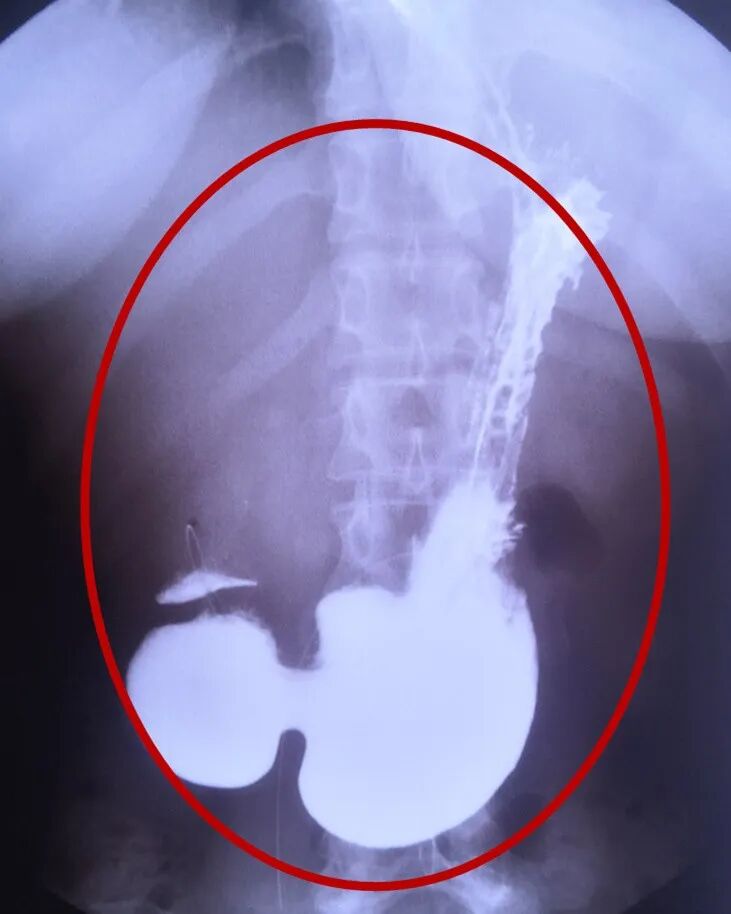

术后食管修复回缩

近日复查上消化道钡餐及CT示恢复良好,食管通畅,已明显回缩,开放良好,胃肠排空好。李大姐现已正常生活。